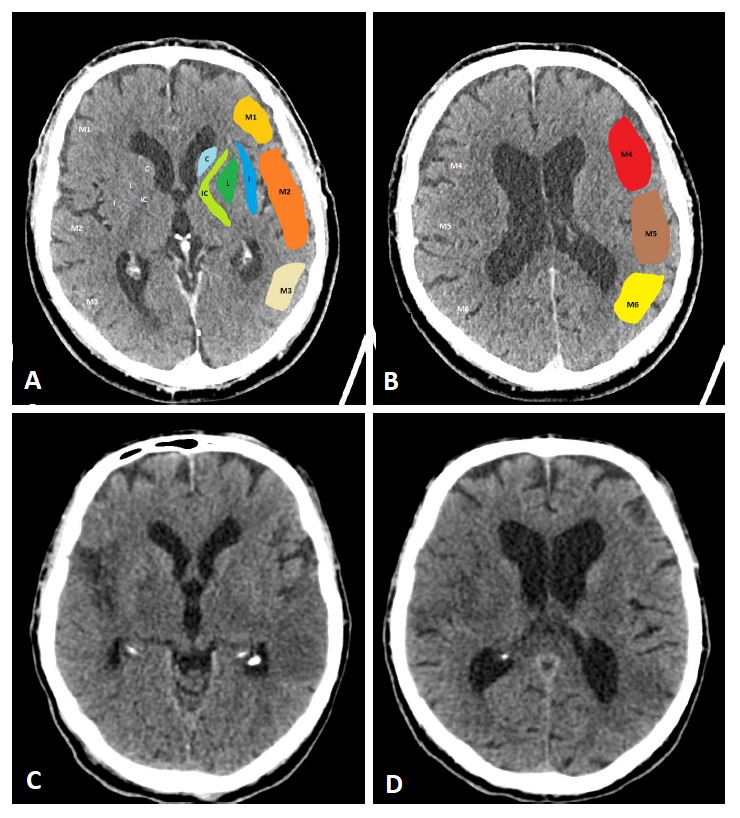

The use of additional perfusion imaging (CT-P or MR-P) in the early time window (within 6 hours of symptom onset) is controversial and is not recommended in routine clinical practice [34, 35, 36, 37]. Perfusion imaging can be used to estimate the infarct core and potential tissue at risk (penumbra). Fig. 2 (Ref. [38, 39, 40]) illustrates CT-P parameters and potential thresholds for both the infarct core and penumbra. These thresholds are debatable and not universally accepted, and may change with the duration of symptoms [38, 40]. In an early time-window, CT-P can overestimate the infarct core, possibly because of a lack of contrast arrival overall [41]. In a pooled analysis from the Highly Effective Reperfusion evaluated in Multiple Endovascular Stroke Trials (HERMES) collaboration, adding CT-P in an early time window has not been found to be associated with functional outcomes [37].

Fig. 2.CT-Perfusion. NCCT ASPECTS 10 (A). CT-A with M2-occlusion (B).

Interpretation of CT-P: the cerebral blood volume (CBV) is symmetrical without a

regional decrease (C). Cerebral blood flow (CBF) is reduced in the posterior MCA

territory on the left (D). The mean transit time (MTT) of the contrast agent (E)

and Tmax (time to maximum; time delay between the contrast agent arrival in the

proximal large vessel arterial circulation and the brain parenchyma perfusion

[F]) are prolonged. The infarct core in CT-P shows a markedly reduced CBF (